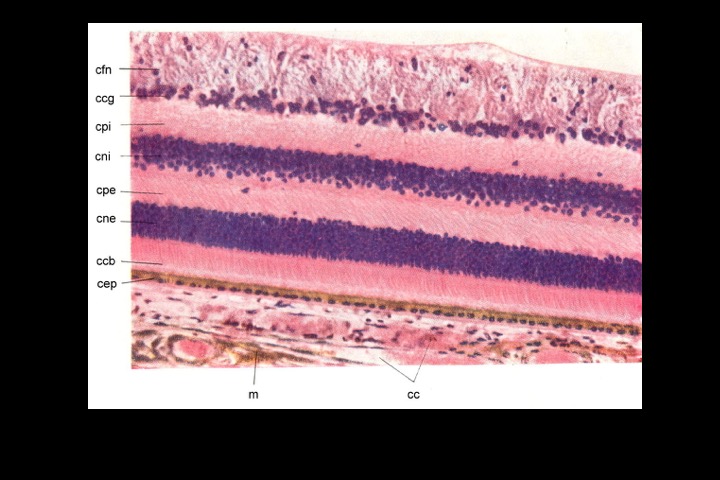

Corte histológico da retina